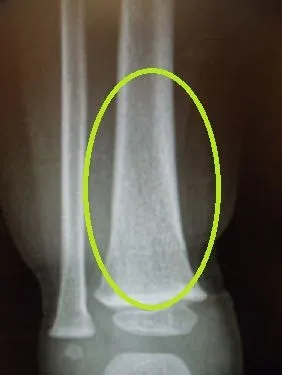

Below is a stress fracture in an ameteur athlete with fracture seen on X-ray, this is also referred to as "the dreaded black line"

Same fracture seen 8 weeks later with bridging across the fracture and fracture callus